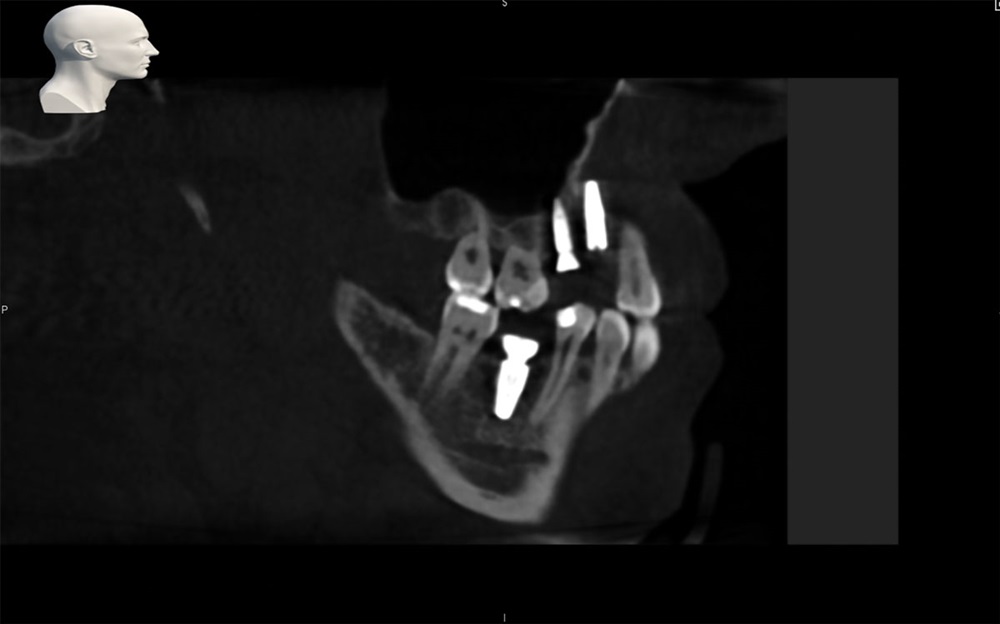

As another case example, see Figs. 11 and 12 showing a single implant placement.

Fig. 12: Final dental implant placement for Case 2.